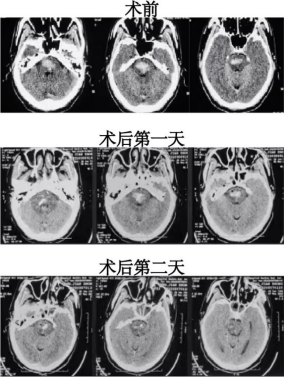

手术前团队进行精细的手术计划,医生们对赵先生脑组织和血管结构进行3D重建,保证在机器人辅助引导下可以精准达到脑干血肿区域。术中不开颅,仅通过钻孔精准到达脑干血肿区域,达到微创的目的,手术仅用1小时就顺利完成。术后第一天进行溶栓治疗,术后第二天复查血肿已大部分清除并拔除头部引流,患者意识明显好转,四肢肌力也显著恢复,并可配合查体。

Sino机器人辅助下脑干出血穿刺引流术前和术后CT